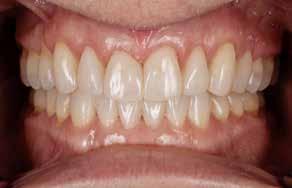

INTRODUKTION OG FORMÅL – Ortodontisk behandling kan være en nødvendighed hos patienter med avanceret parodontitis (stadie 3 og 4), hvis der skal genetableres funktionel okklusion, tilfredsstillende æstetik samt være mulighed for indsættelse af tanderstatninger. Formålet med denne artikel er at præsentere kliniske retningslinjer og en behandlingsmodel for ortodontisk behandling af patienter med velbehandlet parodontitis.

MATERIALE OG METODER – Artiklen bygger på en gennemgang af internationale retningslinjer og kliniske erfaringer, herunder to patienttilfælde, hvor der er foretaget ortodontisk behandling af patienter med stadie 3- og 4-parodontitis. Der beskrives rammer for en systematisk tilgang med fokus på parodontal sundhed, ortodontisk korrektion og livslang vedligeholdelse, hvor hele behandlingen udføres i et tæt interdisciplinært samarbejde.

RESULTATER – Begge patienter opnåede sunde parodontale forhold, funktionel okklusion og forbedret æstetik. Ortodontisk behandling blev iværksat efter opnåelse af parodontal stabilitet og tilpasset det reducerede parodontium med kontrollerede kraftsystemer. Under behandlingen blev parodontiet vedligeholdt, og efter afsluttet ortodontisk behandling blev patienterne fulgt med regelmæssige kontroller af både parodontal sundhed og ortodontisk retention.

KONKLUSION – Ortodontisk behandling af patienter med velbehandlet parodontitis er mulig og kan give gode æstetiske og funktionelle langsigtede resultater med en interdisciplinær tilgang og efterfølgende fokus på vedligeholdelse og retention.